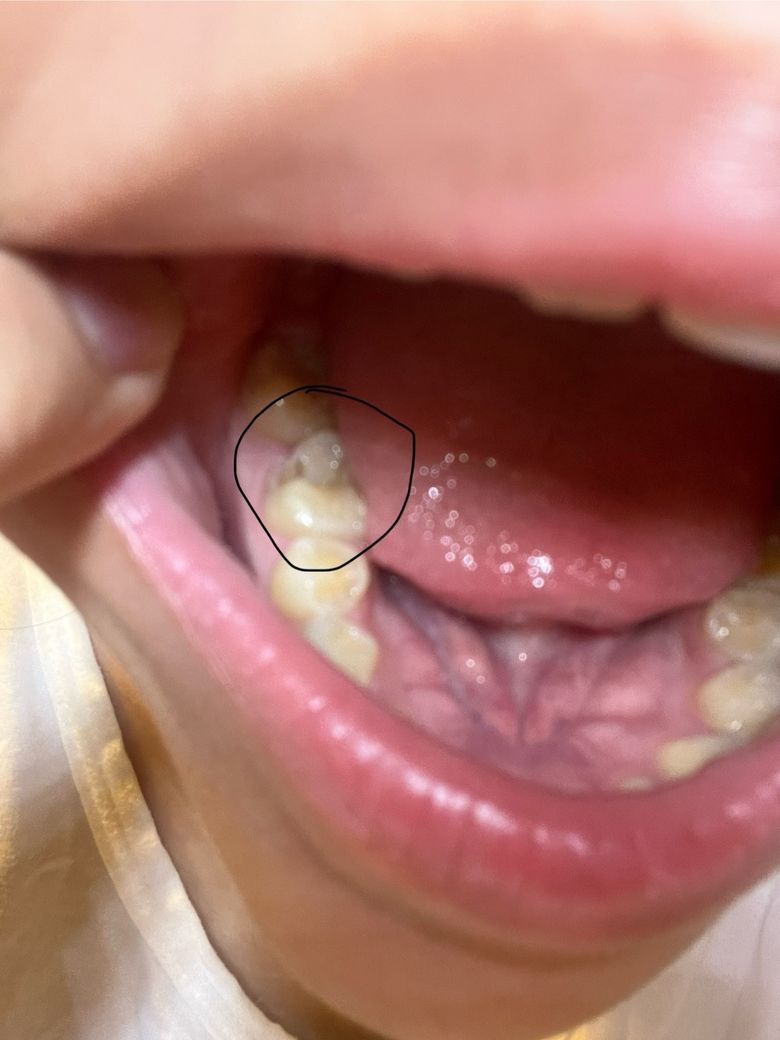

진짜 저 어떡하나요 치과의사분들 중3좀 도와주세요ㅠㅠ

저렇게 왼쪽 어금니 앞쪽 치아가 패여있고 가만히 있어도 욱씬거리고 아픈데 gpt한테 물어보니까 신경치료하거나 잘못하면 발치까지 해야한다는데 저어떡하나요 신경치료 많이 아픈가요 지금 타이레놀로 버티고있는데 통증 나아지지도 않고 계속 아프네요..ㅠ 중3인데 벌써부터 치아 이러면 답 없죠?

일단 치과에 가셔서 엑스레이를 찍어보세요. 유치라면 큰 문제는 아니지만 영구치라면 신경치료를 행될것같습니다.

사진으로 봤을 경우에는 충치가 깊게 생긴 것으로 보입니다. 충치가 있다면 충치를 제거하고 치과용 재료로 충전을 해야 합니다. 충치가 너무 깊다면 신경이 노출되기 때문에 신경치료를 해야 할 수도 있습니다.

자세한 확인을 위해서 치과에서 진료를 받아보는 것을 권유드립니다.

일단은 신경치료를 시도는 해보는데 발치까지도 염두해두어야 할 것 같습니다 상태가 좋진 않습니다

지금 상태라면 신경치료는 가능해보이나 이대로 더 방치하면 발치를 해야할 가능성도 있습니다.